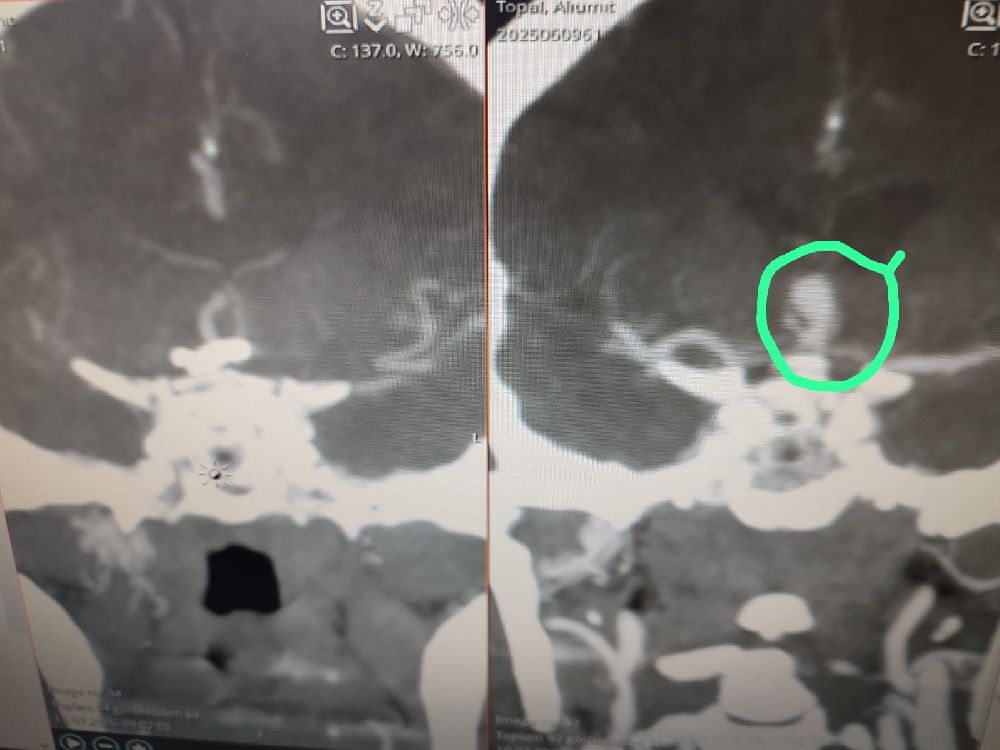

Antalya'nın Serik ilçesinde beyninde baloncuk (anevrizma) tespit edilen hasta, Serik Devlet Hastanesi'nde kaş üzerinden minimal bir kesi ile gerçekleştirilen operasyonla sağlığına kavuştu.

Beyninde anevrizma tespit edilen hasta, Serik Devlet Hastanesi'nde kaş üzerinden minimal bir kesi ile gerçekleştirilen operasyonla sağlığına kavuştu. Beyin ve sinir cerrahisi uzmanları Op. Dr. Ömer Elçik ve Op. Dr. Salim Tekir tarafından uygulanan yeni yöntem sayesinde hastanın ameliyat sonrası sürecinin hem daha konforlu geçtiği hem de estetik açıdan iz bırakmadığı bildirildi. Geleneksel beyin cerrahisinde kullanılan geniş kesiler yerine uygulanan modern teknik, özellikle yüz bölgesinde iz kalmasını istemeyen hastalar için önemli bir gelişme olarak değerlendiriliyor. Operasyonun ardından hasta kısa sürede taburcu edildi.

Serik Devlet Hastanesi Başhekimi Serkan Kurt, bu tür yenilikçi cerrahi tekniklerin hem iyileşme sürecini hızlandırdığını hem de hasta psikolojisine olumlu katkı sağladığını söyledi.